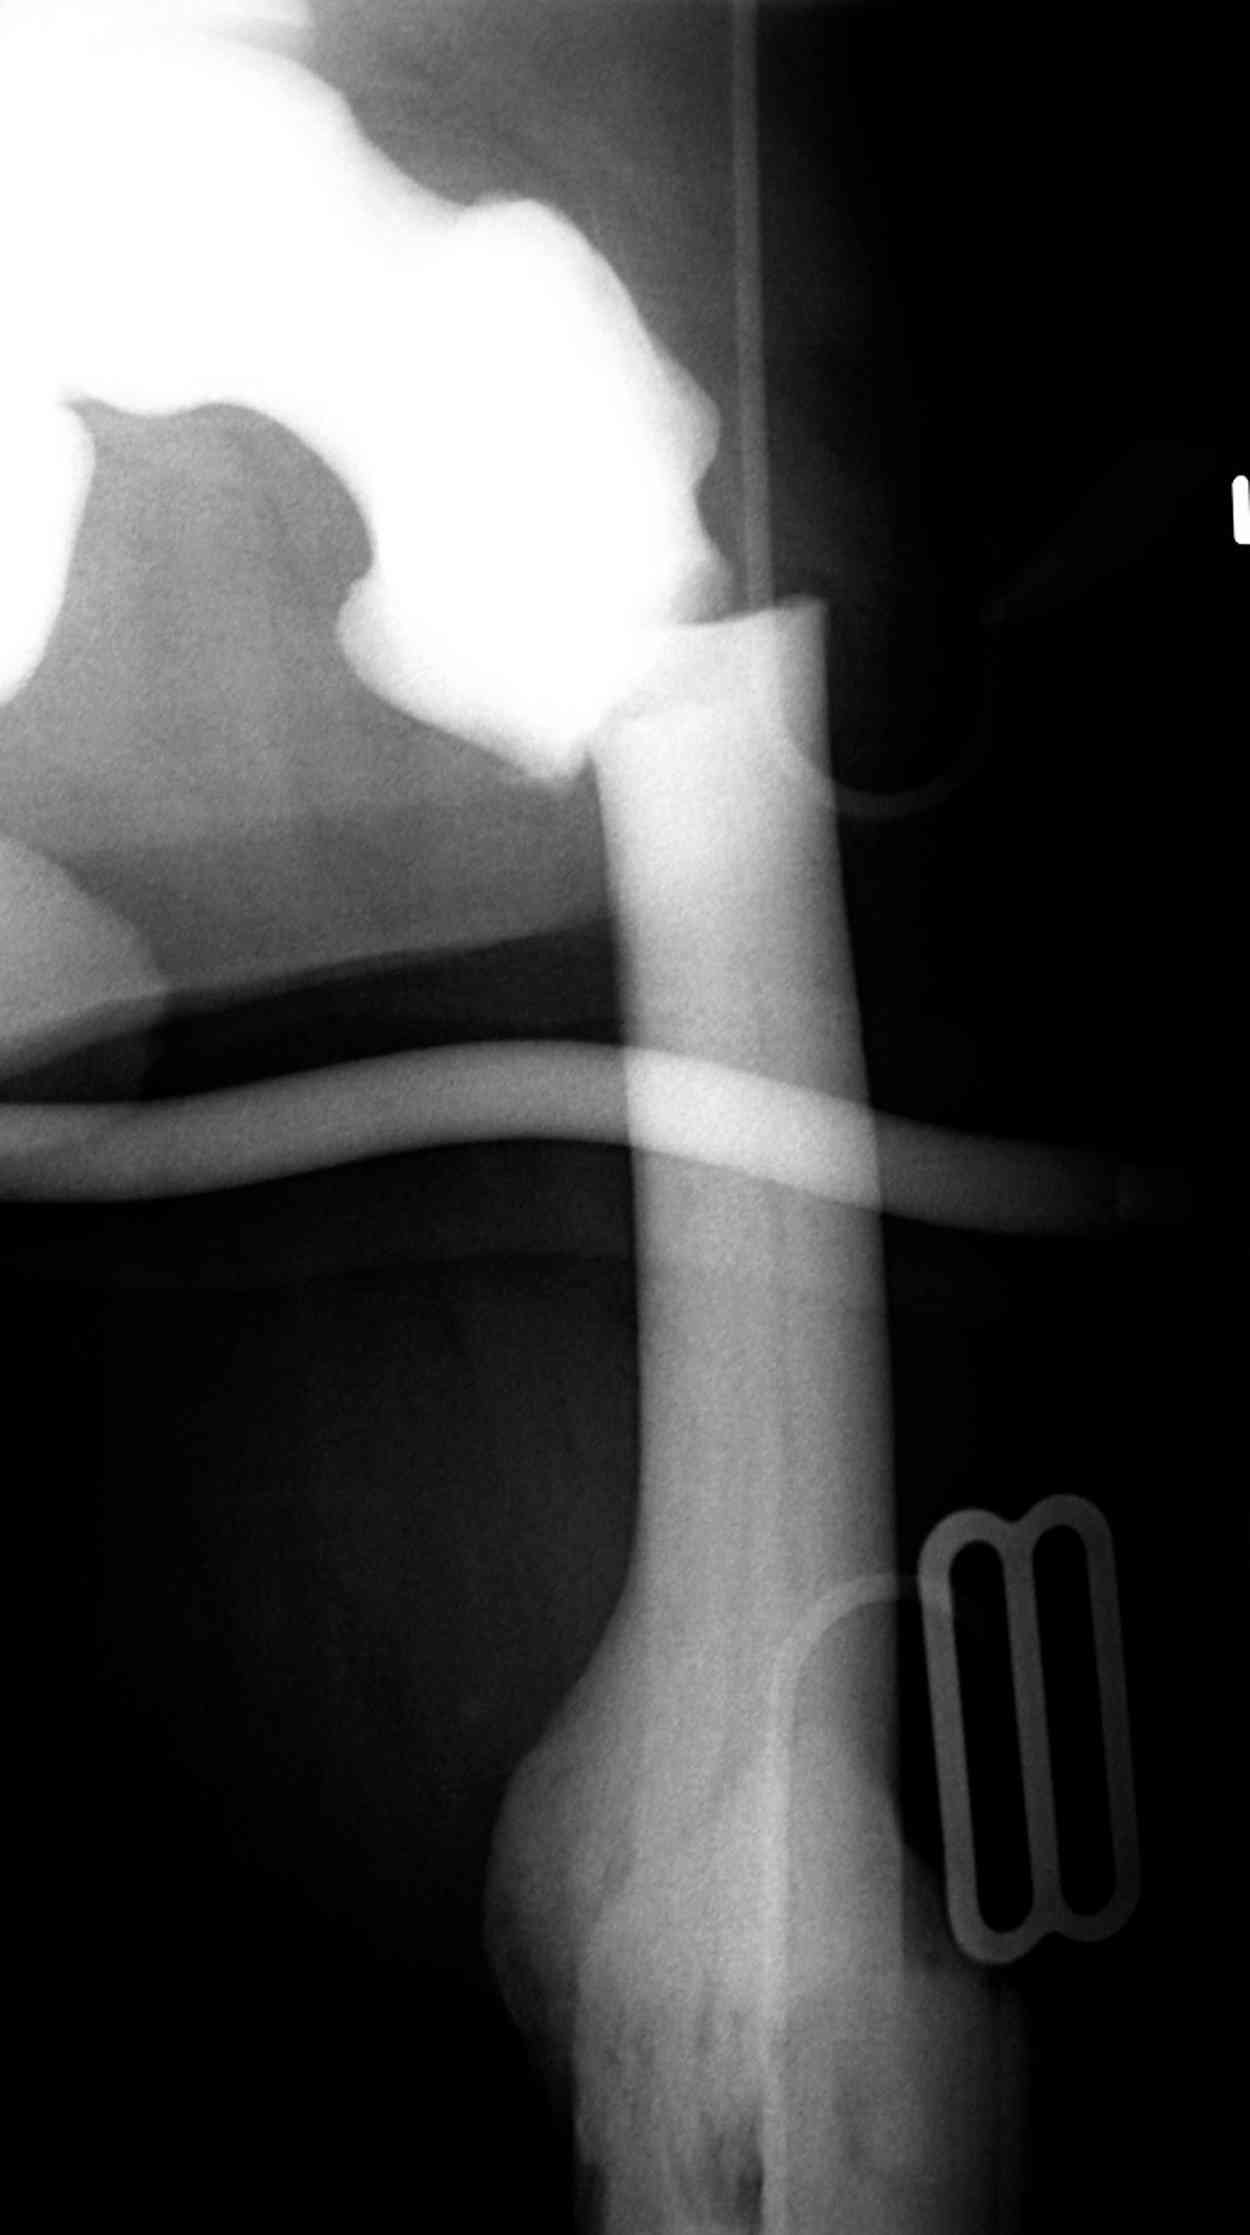

Мужчина, 53 года, жалуется на постоянные ноющие боли в костях голеней, усиливающиеся после ходьбы, боли в коленных суставах. Считает себя больным с 1987 г., когда впервые появились боли в коленных суставах. В 1990 г. выставлен д-з: вторичный ДОА коленных суставов, фиброзная дисплазия костей. После проведенного лечения (НПВП, радоновые ванны, курс введения кислорода в коленные суставы) в течение 5 лет ремиссия. С 1995 г. ежегодные обострения весной и осенью, проявляющиеся болями в коленных суставах, явлениями синовита. Проводилось лечение НПВП, физиопроцедуры, внутрисуставное введение дипроспана с положительным эффектом. С 2004 г. - эффекта от проводимой терапии нет. В 2006 г. впервые по рентгеновским снимкам выставлен д-з: болезнь Альберса-Шенберга. Деформирующий гонартроз справа 2 ст., слева 3 ст. С 2006 г. ездит на лечение в Китай, где проводится лечение радоновыми грязями, массаж с положительным эффектом. Объективно: коленные суставы деформированы, при пальпации б/болезненные. Движения в полном объеме. При ходьбе хромает. Диагноз: болезнь Алберс-Шонберга. Деформирующий гонартроз справа 2 ст., слева 3 ст.Хотелось бы уточнить диагноз и определить тактику дальнейшего лечения. Заранее спасибо.

Представленные Вами данные о пациенте 57 дет с болезнью Альбертс-Шенберга чрезвычайно интересны, но диагноз вызывает большие сомнения. Для мраморной болезни характерно прееобладание склероза, а на представленных рентгенограммах преобладает симметричная дезорганизация архитектоники губчатой кости в эпиметафизарной зоне дистальных отделов бедер и голеней.

Мне кажется, представленные рентгенограммы скорее соответствуют варианту фиброзной дисплазии который был описан М. Campanacci (1976) или

обызвествляющей фиброме H.E.Schlitter (1958).

Уважаемый Константин Иванович! Полностью согласен с проф. Михайловым, данный случай не похож на мраморную болезнь, при которой имеется резкое, строго симметричное и генерализованное уплотнение костной ткани (остеопетроз), и кость оказывается построенной преимущественно из гомогенного компактного костного вещества. Для примера привожу случай из архива нашего института (бедренные, плечевые кости и таз, рис 1,2,3)

Изменения структуры костей у Вашего пациента больше похожи на полиоссальную форму фиброзной дисплазии или болезнь Педжета, возможены также инфаркты костного мозга б.берцовых костей. К сожалению, качество снимка не очень хорошее, непонятно, сохранен ли кортикальный слой б.берцовых костей по передней поверхности.

Для примера привожу случай из архива американской ассоциации рентгенологов (ACR) - развитие злокачественной фиброзной гистиоцитомы на левой б.берцовой кости у пациента с множественными инфарктами костного мозга (рис 4,5 - левая, рис 6 - правая)

Не являюсь специалистом по костной патологии, но мне кажется, на ренгенограмме множественные мета-диафизарные образования напоминяющее змееподобных извилистых линии и периостеальные ламинирование очень напоминяет картину остеонекроза (инфаркта) костей, возможно связано с длительным применением стероидов.

слайды из прошлегодного случая.